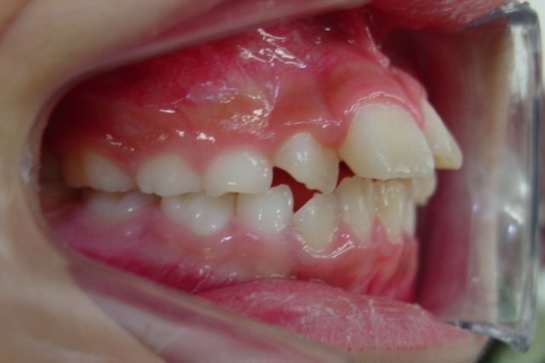

途中経過